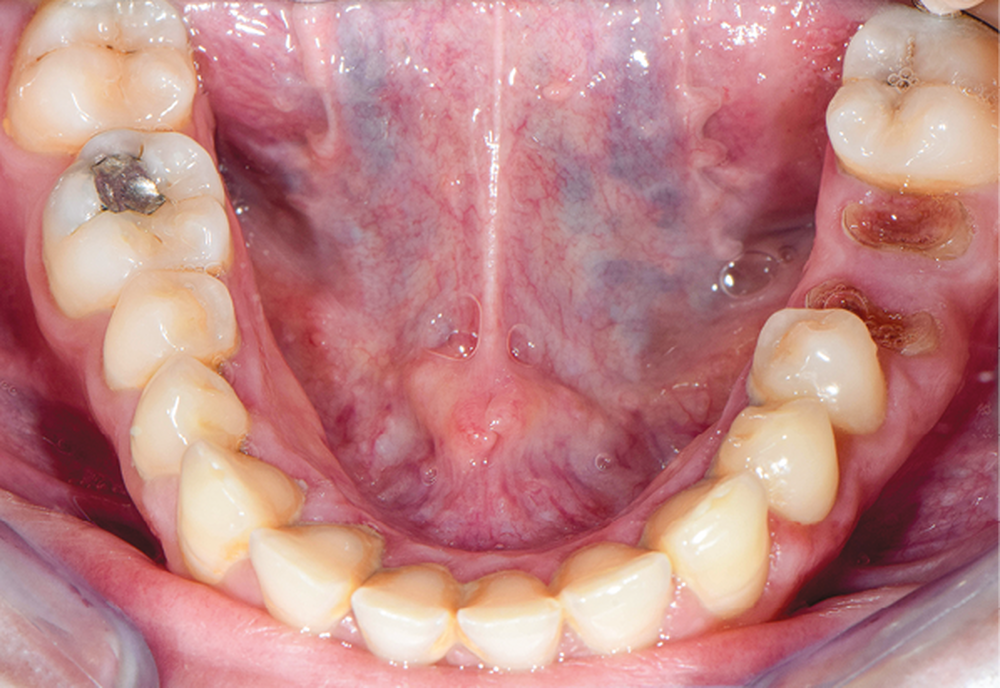

À l’examen endobuccal (fig. 1), une inflammation marginale et papillaire sur un parodonte de biotype fin est visible. Une gingivite généralisée induite par la plaque bactérienne est donc diagnostiquée.`

La ligne du sourire est inversée, malgré une perception atténuée par la présence de deux couronnes à armature zircone sur 11 et 21 réalisées une dizaine d’années auparavant. On note une irrégularité et une asymétrie de forme des festons gingivaux, ainsi qu’une dysharmonie de forme des incisives et canines quant à leur proportion.

L’arcade maxillaire présente des signes d’usure érosive caractéristiques d’attaques acides : surface lisse, de couleur satinée, présence d’un pourtour d’émail sain en regard du sulcus, et effacement des morphologies dentaires telles que la disparition des cuspides palatines des prémolaires et de la 16. En revanche, 26 et 46 ne présentent aucun problème d’usure. La patiente ne rapporte pas de signes d’hyperesthésie dentinaire. Par ailleurs, la dimension verticale d’occlusion (DVO) étant conservée, la patiente présente une usure majeure compensée par l’égression dentaire (ce qui montre une évolutivité lente).

L’arcade mandibulaire présente un pseudo-édentement de classe III de Kennedy (36 à l’état de racines).